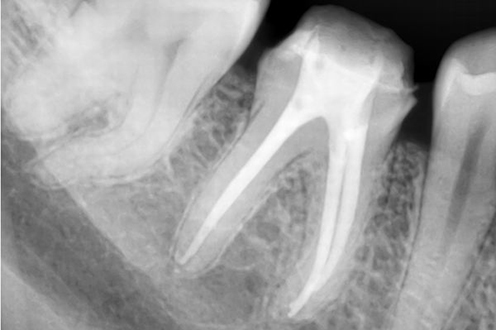

Endodoncija je terapijski postupak u dentalnoj medicini koji podrazumijeva liječenje upale zubne pulpe (zubnog živca) unutar korijenskih kanala zuba nastalu djelovanjem bakterija uslijed uznapredovalog karijesa. Terapijski postupak koji se izvodi pod lokalnom anestezijom sastoji se od uklanjanja inficirane zubne pulpe iz korijenskih kanala zuba, njihova čišćenja i dezinficiranja te punjenja biokompatibilnim materijalima namijenjenima za tu svrhu. Poslije završene terapije na zub se stavlja ispun (plomba), a ako je zubna kruna jače oštećena, moguća je nadogradnja i krunica. Cilj endodontskog liječenja zuba je sprječavanje širenja upale iz korijenskog kanala na kost oko korijena zuba te očuvanje zuba u usnoj šupljini.

Revizija punjenja korijenskih kanala podrazumijeva uklanjanje postojećeg punjenja iz korijenskog kanala, ponovno čišćenje, dezinfekciju te ponovno punjenje korijenskog kanala zbog razvoja upale (granuloma) u području kosti oko samoga korijena. Takva upala najčešće nastaje zbog neadekvatnog prethodnog čišćenja i punjenja korijenskog kanala ili zbog dugotrajne prisutnosti neliječene upale zubnog živca u korijenskom kanalu. Prisutnost takve upale može biti praćena bolovima u zubu (najčešće na zagriz) i postojanjem fistule (prištića) na sluznici usne šupljine u području vrha korijena zuba. Međutim, često takva upala koja se razvija godinama nije praćena nikakvim simptomima ili je slučajan nalaz na ortopan snimci. Ponovljenim liječenjem nastoji se smanjiti broj bakterija u korijenskom kanalu koje su uzročnici takve upale te se potpunim brtvljenjem korijenskih kanala i stavljanjem ispuna sprječava daljnji ulazak bakterija iz usne šupljine kroz korijenski kanal u kost čime se omogućava organizmu da sam izliječi nastalu upalu.